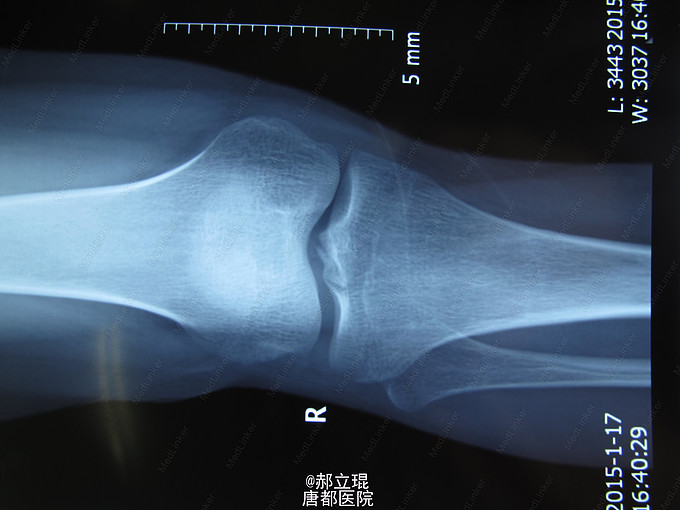

车祸伤致右膝疼痛,活动受限6小时入院。男性,30岁,6小时前车祸伤导致右膝膝关节疼痛,活动受限。全身情况良好。

专科情况:右膝肿胀,压痛阳性,活动受限,右下肢血运良好,无明显神经症状。抽屉试验阳性。侧方应力试验阴性。